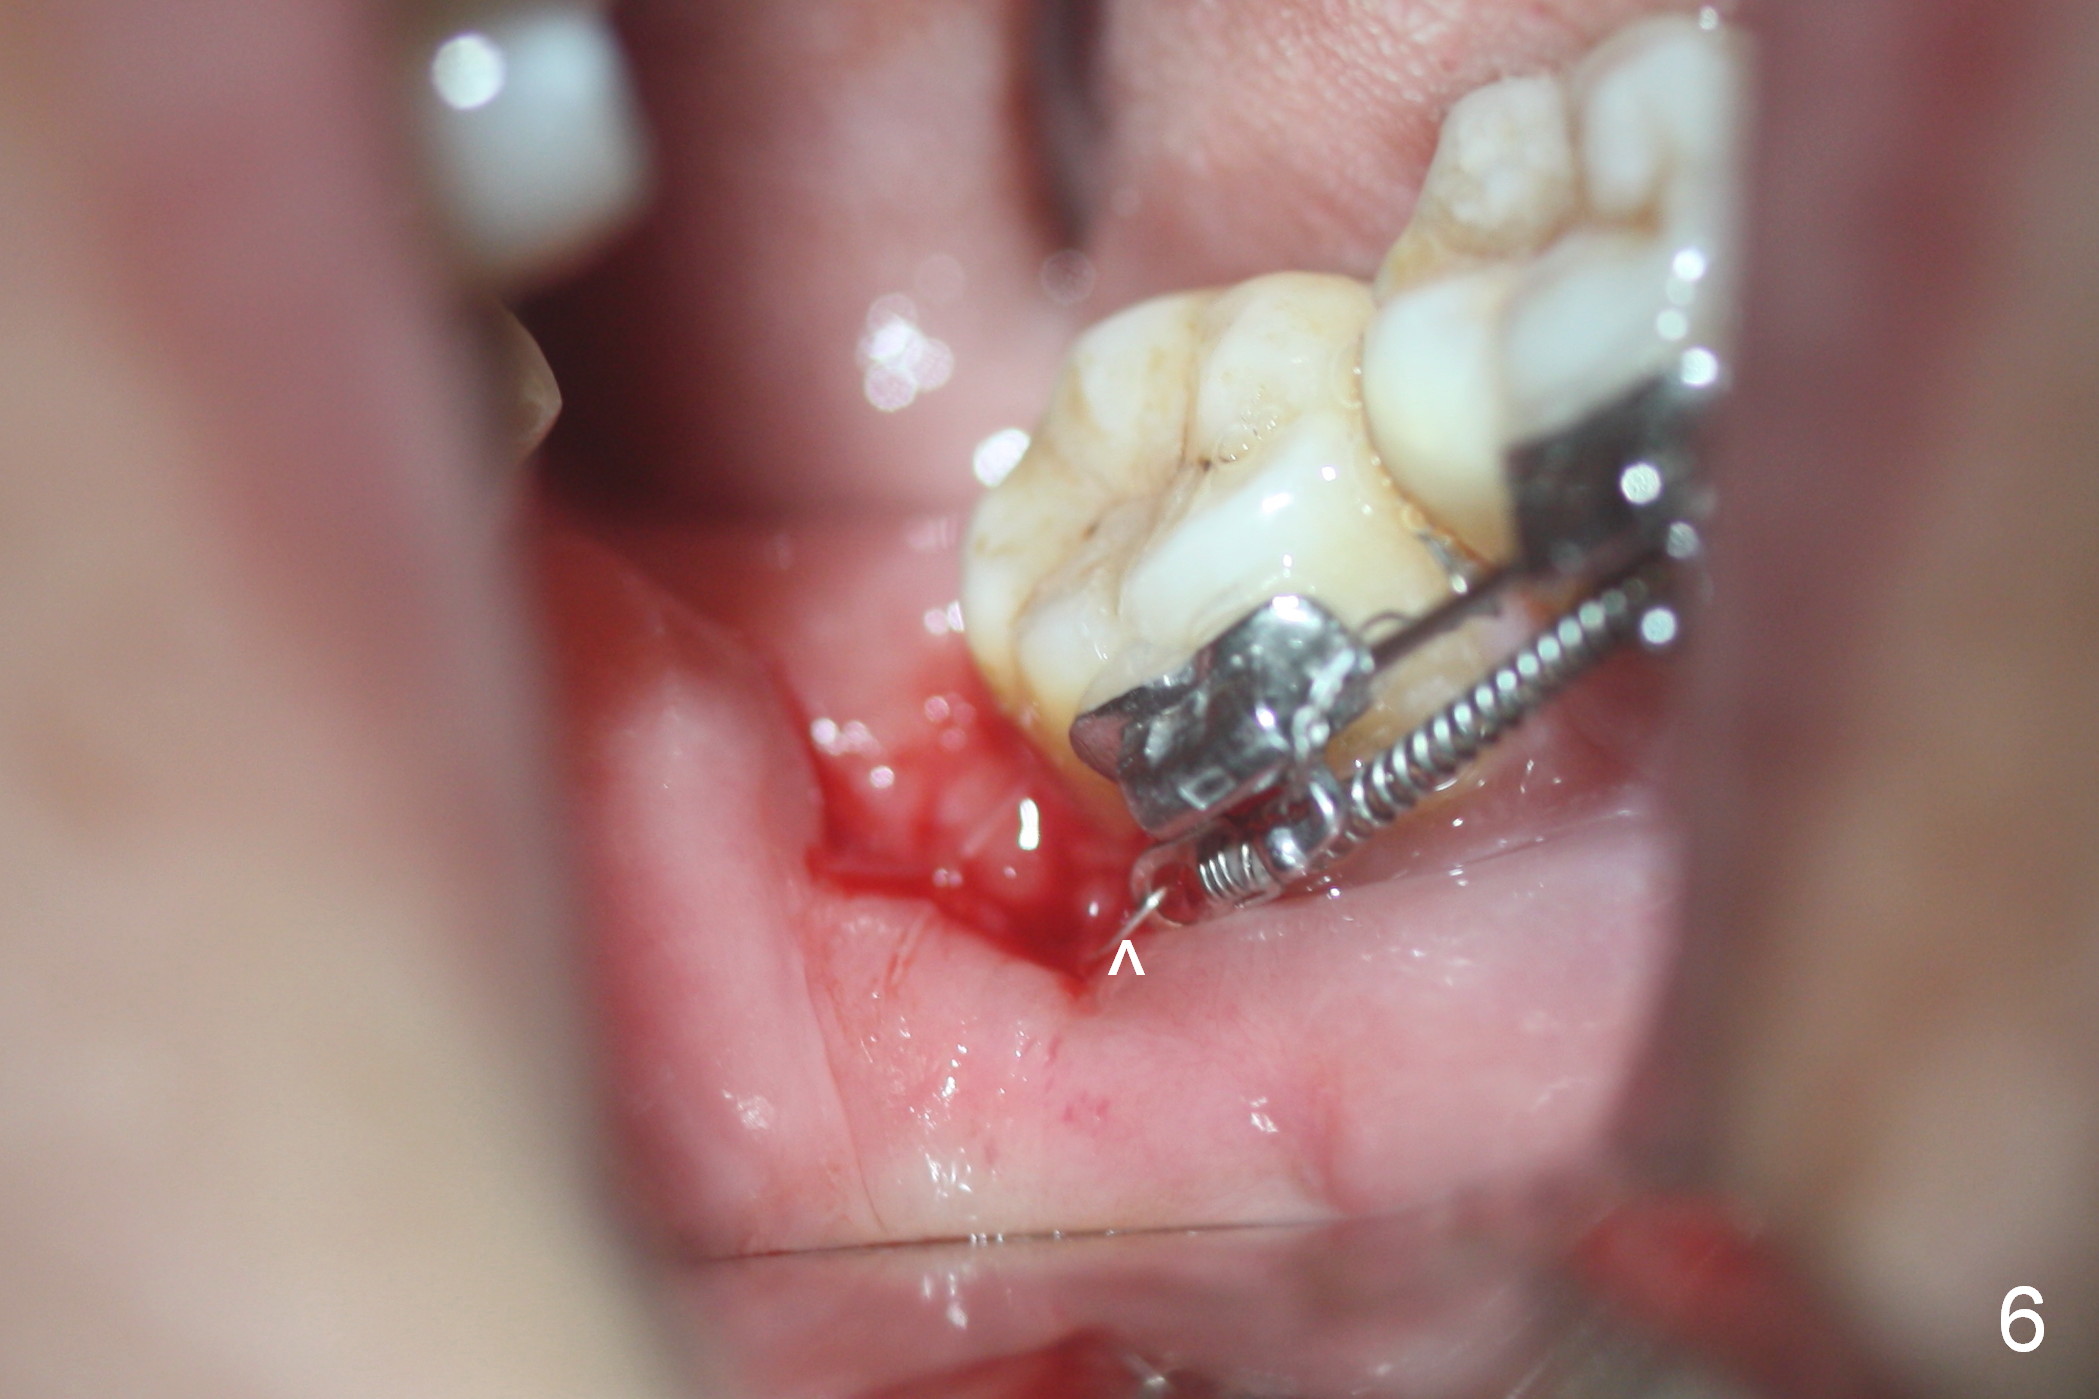

A 47-year-old lady has lost the lower right 1st molar for long time; with reduction of the buccolingual width (Fig.1) and mesiodistal width (Fig.2,3). With regional orthodontic appliance (Fig.4) for 3 months, the tooth #29 has started being distalized (Fig.5). One month and a half later, the tooth #26 starts to shift labially. Power chains and then closed coil spring are placed between #29 and 32. #29 distalization is slow (Fig.7) with closure of the diastema between #31 and 32 (Fig.8, as compared to Fig.1,3). Seven months post banding, a 10 mm miniimplant is placed distobuccal to the tooth #32 (Fig.6); the same 12-mm closed spring is stretched distal by ~ 6 mm (Fig.8 between arrowheads). Two months later, #29 is more distalized (Fig.9 tilted) with bone deposit mesially (*) and coronally (^). A .018' stainless steel wire is installed with an open coil spring placed between #28 and 29 (Fig.10 (^),11). Note #29 rotation (Fig.11). To solve the tilting, a power hook (Fig.12 black) will be clamped to a .016x.016 wire (red), while the closed spring is lowered and attached to the power hook (Fig.12 white). Take photos after removing the existing wire occlusally to show the alveolar width change. When the wire is placed, make sure that the distal wings of #29 bracket is fully engaged to reduce the tooth rotation. Make occlusal adjustment on #31 and 32 to reduce anterior open bite.

Once the ligature wire connecting the mini implant and closed coil spring fractures inside the wound, it is difficult to replace, causing localized inflammation (Fig.13, 8 months post placement). The wire and the mini-implant need a 2nd difficult surgery for removal.